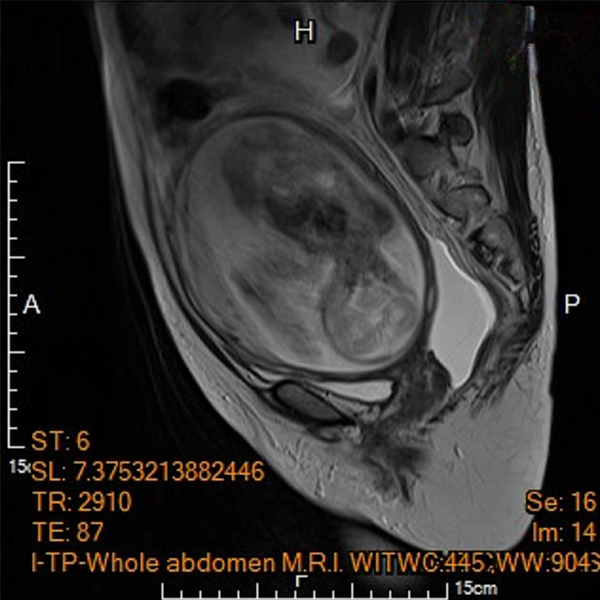

為該名孕婦產檢的馬偕紀念醫院高危險妊娠科資深主治醫師王亮凱表示,李小姐在妊娠20週進行第四次例行性產檢時,腹中胎兒發育情況一切正常,但超音波檢查意外發現孕婦腹腔內積滿大量腹水,及左側下腹部有一個15公分大小、邊界模糊、結構複雜的卵巢腫瘤,孕婦反映有明顯的進食與呼吸困難疑似腸胃道問題,為求謹慎,針對腹水檢體進行細胞檢驗,雖未能於腹水內發現癌細胞,腹部核磁共振影像顯示腫瘤疑似來自左側卵巢,且惡性風險極高,高度懷疑是懷孕中合併卵巢癌。

陳楨瑞表示,李小姐手術前,血液檢查發現異常超高的抗穆勒氏荷爾蒙(AMH)指數(正常育齡女性數值介於2-5,此孕婦為>22.5,因超越檢查極限無法顯示正確數值),已經強烈懷疑為卵巢顆粒細胞癌!手術採傳統直式開腹,在不造成腫瘤破裂的情況下,順利切除包含惡性腫瘤的左側卵巢輸卵管,並取部分大網膜組織進行病理檢驗,幸運的是,手術時於腹腔內並沒有發現腫瘤擴散或轉移跡象,因而子宮與右側卵巢輸卵順利保留,子宮內胎兒也未受到手術影響。病理報告雖證實為卵巢癌,但是歸屬於低度惡性之「幼年型顆粒細胞瘤」,免於後續在懷孕期間接受化學治療。李小姐術後恢復極佳,先前因腹水引起的腹脹、呼吸困難等症狀也完全消退,孕程得以順利延續。